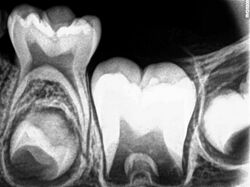

Radiograph of lower right (from left to right) third, second, and first molars in different stages of development

X-ray of teeth of a boy aged 5 years showing left lower primary molar and developing crowns of left lower permanent premolar (below primary molar) and permanent molars

Tooth development or odontogenesis is the complex process by which teeth form from embryonic cells, grow, and erupt into the mouth. For human teeth to have a healthy oral environment, all parts of the tooth must develop during appropriate stages of fetal development. Primary (baby) teeth start to form between the sixth and eighth week of prenatal development, and permanent teeth begin to form in the twentieth week.[1] If teeth do not start to develop at or near these times, they will not develop at all, resulting in hypodontia or anodontia.